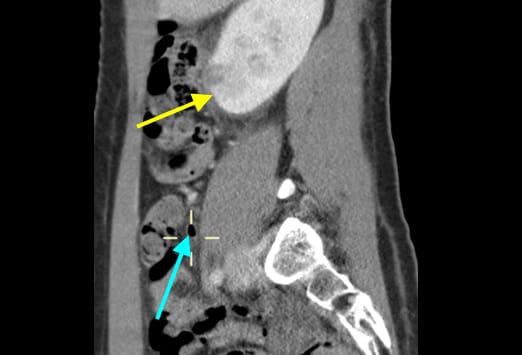

Die Abbildung auf der linken Seite zeigt eine einfache Appendizitis. Hier ist eine Verbreiterung und ein Ödem der Appendix zu sehen, mit einer erhöhten Kontrastmittelaufnahme der Appendixwand (blauer Pfeil) und einer geringen umgebenden Entzündungsreaktion. Beim Fortschreiten einer Appendizitis kommt es von der einfachen Form und einer nachfolgenden gangränösen Veränderung schließlich zur Perforation. Nach der initialen Obstruktion des Lumens kann es zu einer verminderten Perfusion kommen. Das Bild auf der rechten Seite zeigt eine gangränöse Appendizitis, bei welcher es zu einer Zunahme und einer Infiltration in das Mesenterium gekommen ist. Ein Appendikolith (gelber Pfeil) kommt ebenfalls zur Darstellung.